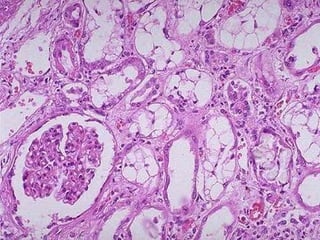

Necrosi tubulare acuta da mioglobina

Necrosi tubulare acuta da bilirubina